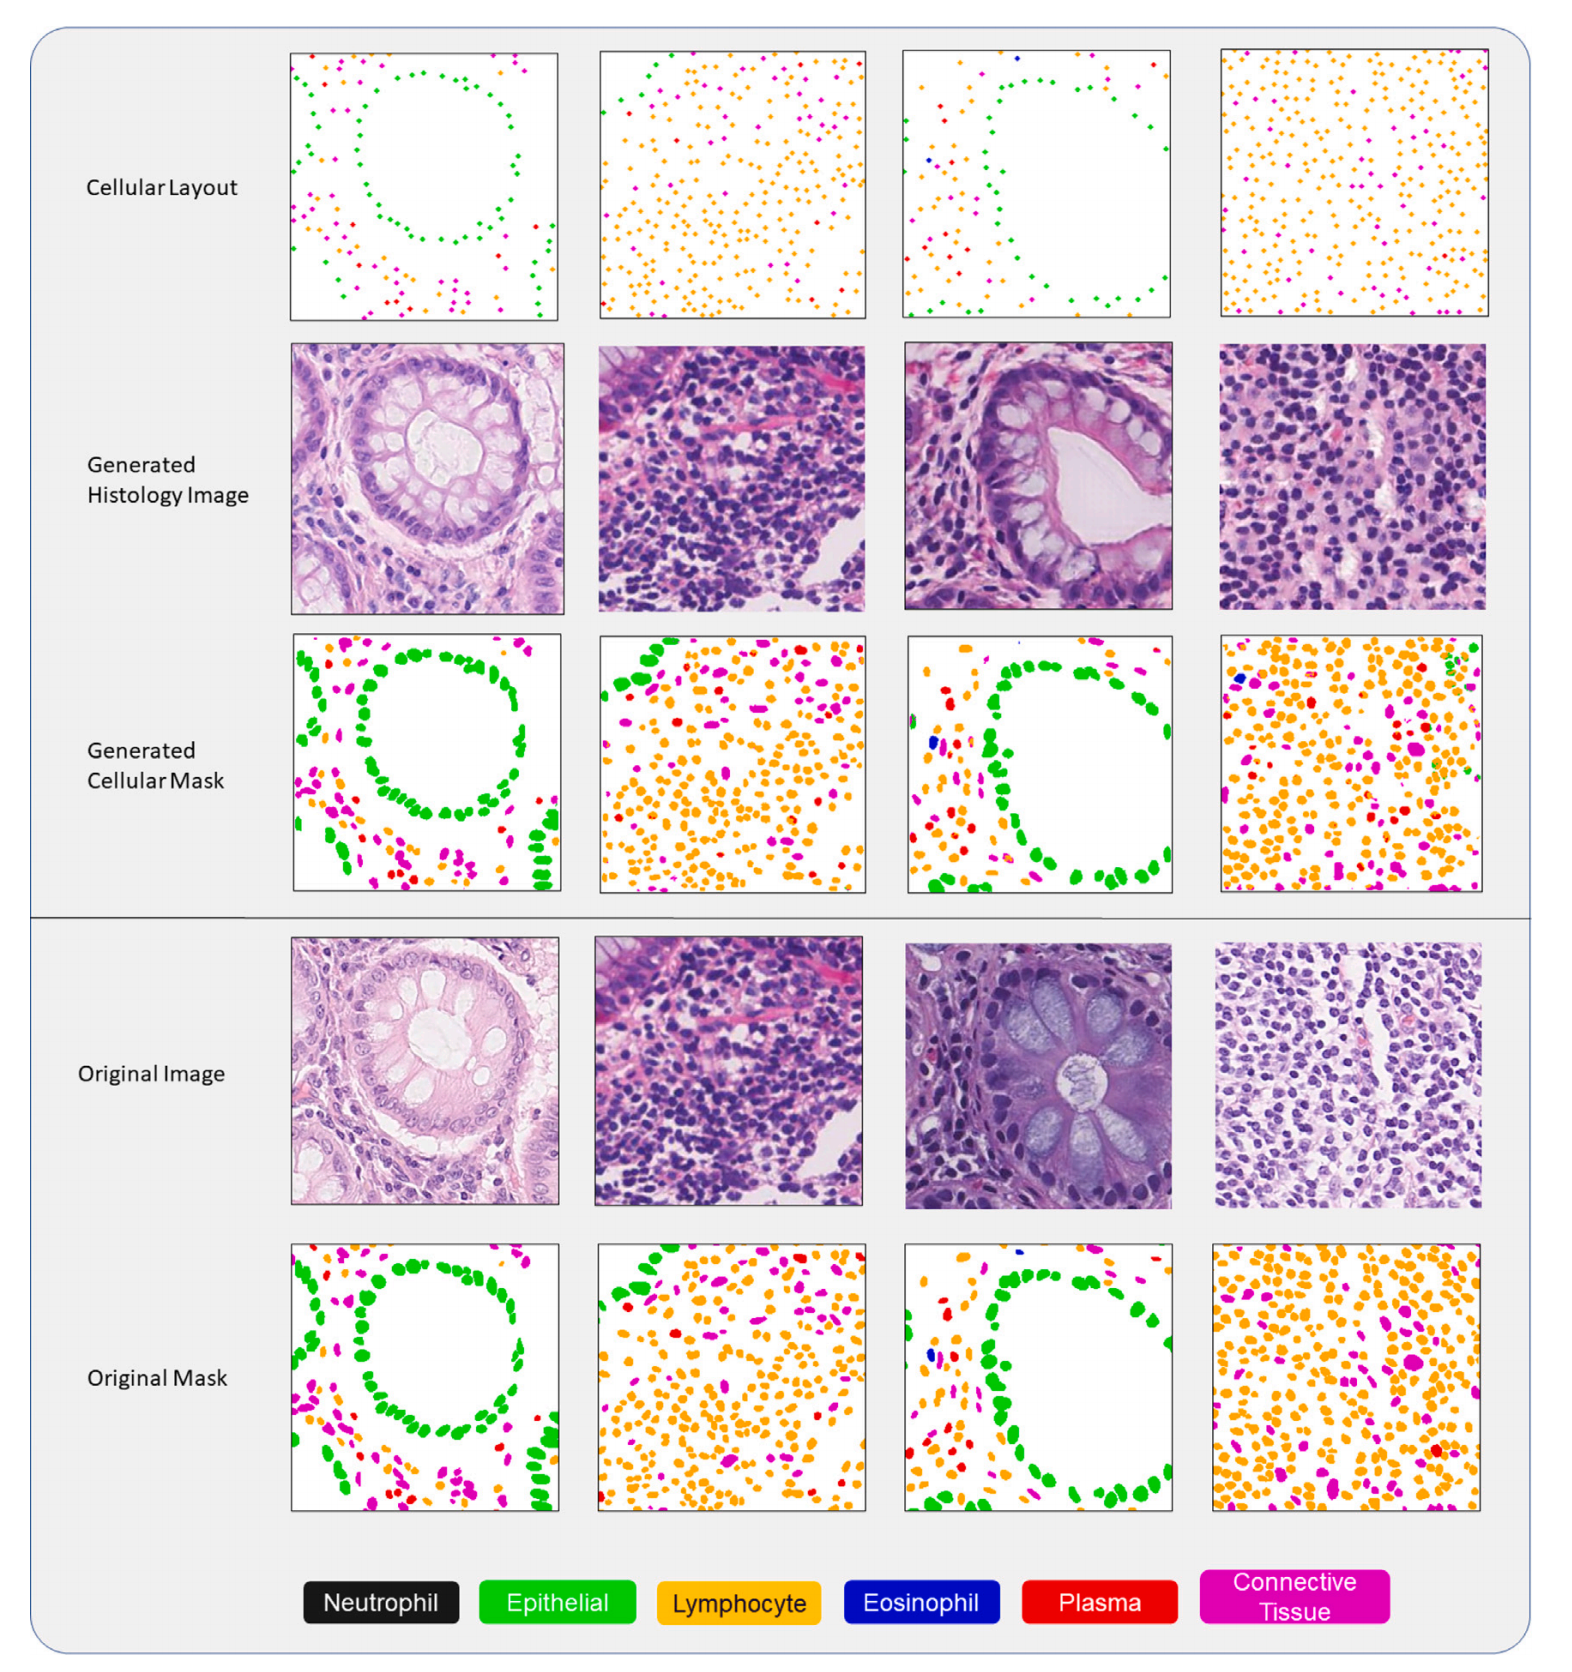

重点关注

Fig. 3 展示了从 CoNiC 数据集中生成的图像样本以及细胞核分割掩模。在细胞布局的最顶行中,不同类型的细胞以不同的颜色显示位置。

分析这个图表时,我们可以注意到以下几点:

-

细胞类型的可视化:图中最顶行展示了不同类型细胞的布局,每种类型的细胞都用不同的颜色来表示,这有助于用户快速识别和区分不同类型的细胞。

-

细胞核分割掩模:在生成的图像中,细胞核被准确地分割出来,并且每个细胞核的边界都被清晰地标记。这表明 SynCLay 框架在核分割方面表现出色,能够为每个细胞生成精确的掩模。

-

图像质量:生成的图像在视觉上与真实的组织学图像非常相似,保持了组织结构的细节,如腺体的形状、细胞的形态特征等。

-

真实感:图中展示的合成图像具有很高的真实感,这可以从细胞的分布和组织结构的自然外观中看出。

-

应用潜力:通过展示不同细胞类型的精确布局和分割,图表强调了 SynCLay 框架在计算病理学中的潜在应用,如算法开发、教育、临床质量保证等。

-

定制化能力:由于 SynCLay 允许用户定义细胞布局,这意味着可以生成具有特定细胞类型和分布的定制图像,这对于研究特定病理条件或进行教育演示非常有用。

-

对比与评估:通过将生成的图像与真实图像进行比较,可以评估 SynCLay 生成图像的质量,这对于进一步改进模型和验证其在实际应用中的有效性至关重要。

综上所述,Fig. 3 有效地展示了 SynCLay 框架在生成高质量、逼真的组织学图像方面的先进能力,并通过视觉化的方式突出了其在细胞分割和图像合成方面的准确性和应用潜力。